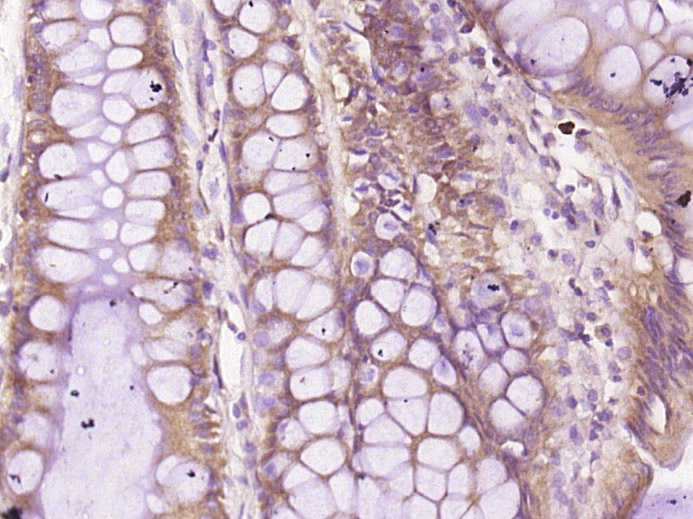

Paraformaldehyde-fixed, paraffin embedded (human liver carcinoma); Antigen retrieval by boiling in sodium citrate buffer (pH6.0) for 15min; Block endogenous peroxidase by 3% hydrogen peroxide for 20 minutes; Blocking buffer (normal goat serum) at 37°C for 30min; Antibody incubation with (Galectin 10) Polyclonal Antibody, Unconjugated (bs-13266R) at 1:400 overnight at 4°C, followed by operating according to SP Kit(Rabbit) (sp-0023) instructionsand DAB staining.

Paraformaldehyde-fixed, paraffin embedded (human colon carcinoma); Antigen retrieval by boiling in sodium citrate buffer (pH6.0) for 15min; Block endogenous peroxidase by 3% hydrogen peroxide for 20 minutes; Blocking buffer (normal goat serum) at 37°C for 30min; Antibody incubation with (Galectin 10) Polyclonal Antibody, Unconjugated (bs-13266R) at 1:400 overnight at 4°C, followed by operating according to SP Kit(Rabbit) (sp-0023) instructionsand DAB staining.